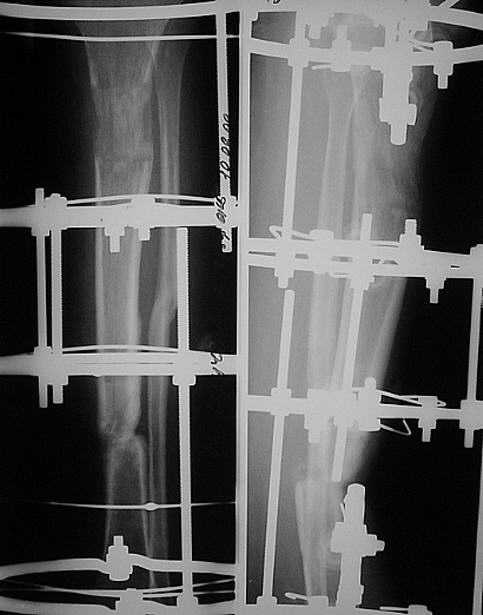

сделан первый этап операции: остеосинтез спице-стержневым аппаратом 7.11.09 г. выполнен второй этап - БИОС с рассверливанием канала, операция прошла без ожидаемых трудностей, открывать зону ложного сустава не пришлось. Прошу сделать замечания.

Виктор Попов, Караганда.

Рекурвация вроде осталась. Недорепонировали на этапе ЧКО.

И точка входа слишком низко.

И гвоздик коротковат imho.

Мы бы сделали заход через переднее межмыщелковое поле, тогда бы динамический блокирующий винт в овальном отверстии прошёл бы через нормальную кость, а не через регенерат. Ну, и стержень, соответственно, потребовался бы длиннее.

Уважаемый коллега! Однозначно надо было произвести первичную динамизацию!!! Мне кажется в целом не плохо сделано, если пациент еще в стационаре не поздно убрать статические винты. Иначе остеотомированный м/б кость ч/з 3 нед срастется и будеть распоркой. С уважением Ерсин Жунусов.

"Рекурвация вроде осталась. Недорепонировали на этапе ЧКО. точка входа слишком низко динамическое блокировани, гвоздик коротковат imho

Небольшие технические погрешности вряд ли кардинально повлияют на окончательный результат. Я бы поздравил уважаемого Виктора с успешным решением трудной задачи с использованием новой технологии и, самое главное, больную с реальным появлением надежды на выздоровление после длительного периода применения предшествующей конструкции с сомнительным прогнозом на исход.